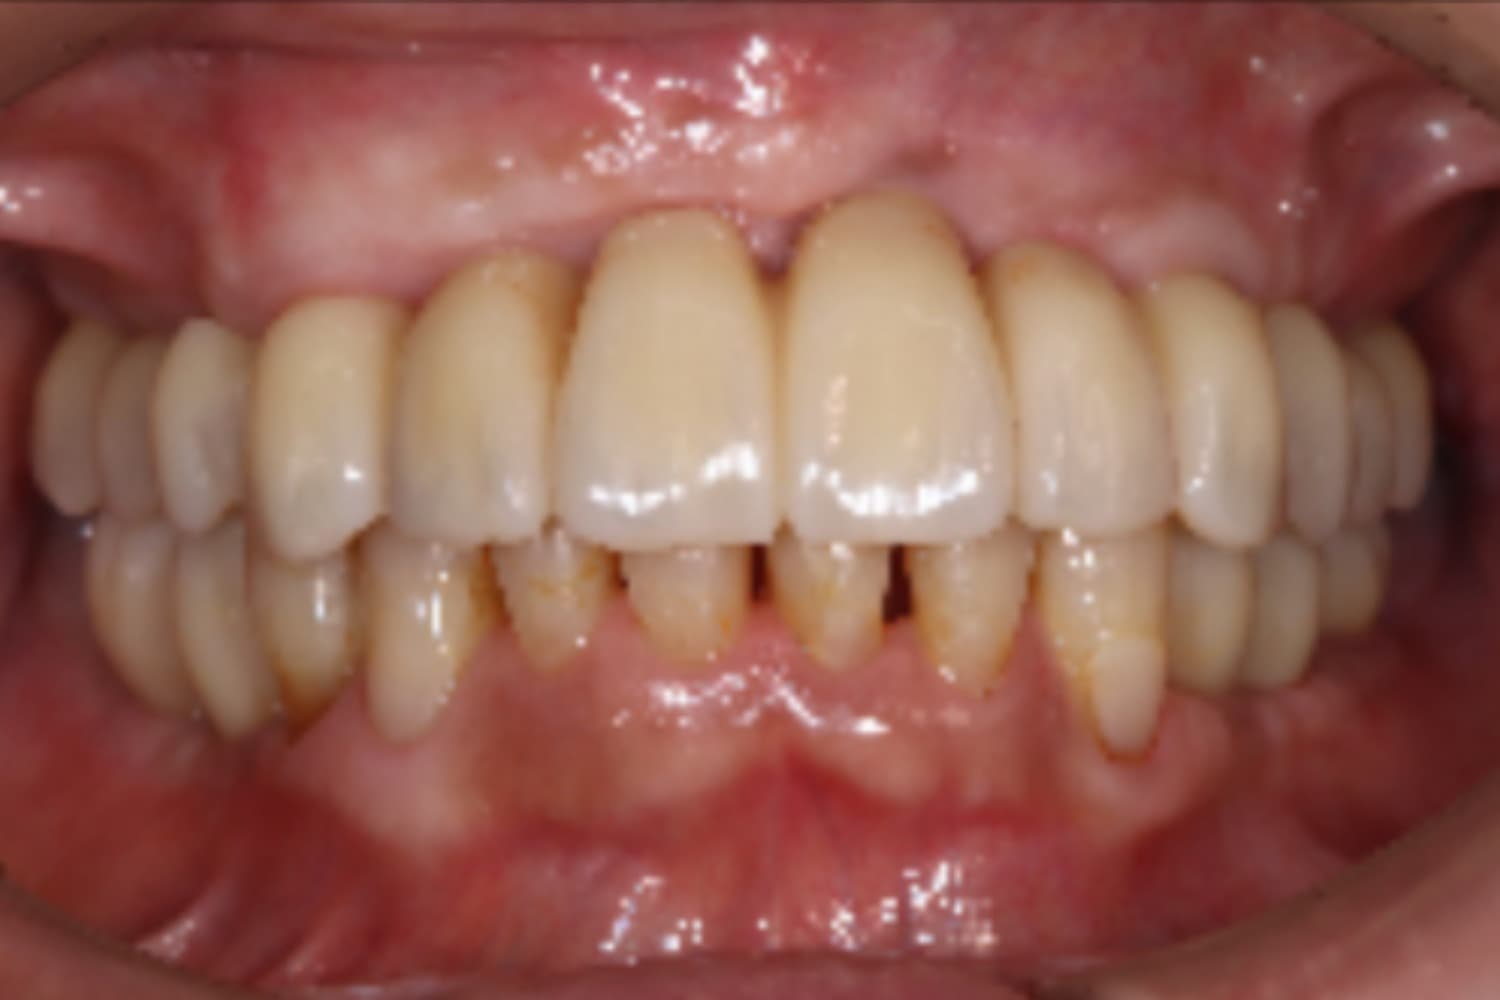

前歯のインプラント治療

Before

After

前歯4本を抜歯し、その後2本のインプラントと骨造成を行いました。上部構造は4本分です。

主訴

前歯が気になる

治療期間

12カ月

治療回数

12回

費用

1,276,000円

副作用・リスク

・重度歯周病により、感染リスクが高い ・インプラントとの結合不良が起きる可能性がある ・手術前に歯周病の十分なコントロールが必要 ・治療後も1〜2カ月ごとの定期メインテナンスが必須